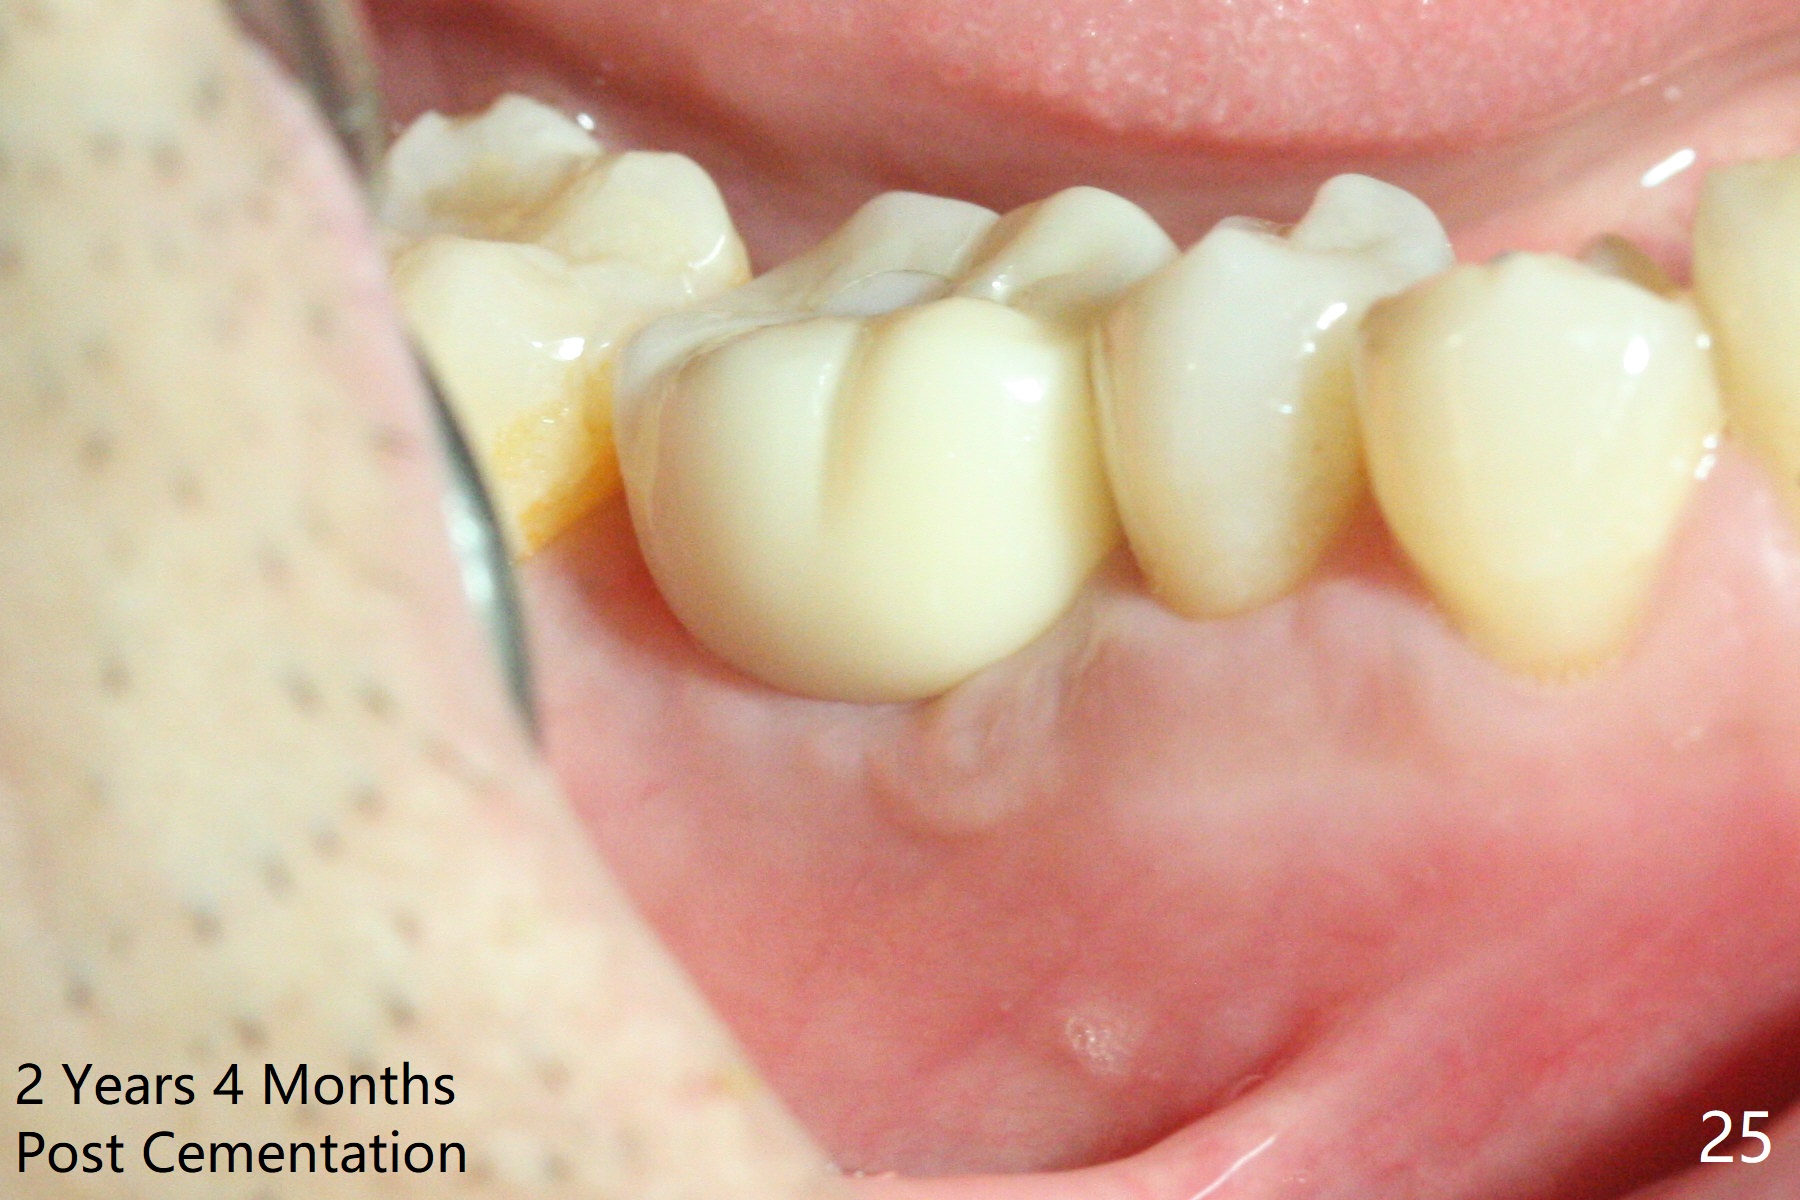

Three weeks later (5.5 months postop), a permanent crown tries in with healthy keratinized gingiva (Fig.18). The provisional keeps normal gingival bed (Fig.19), while the abutment forms tissue cuff (Fig.20). After cementation, PA shows bone regeneration (Fig.21). The gingiva remains healthy 8.5 months post cementation (Fig.22). Bone density around the implant increases 1 year 2 months post cementation (Fig.24). The gingiva remains healthy 2 years 4 months post cementation (Fig.25).